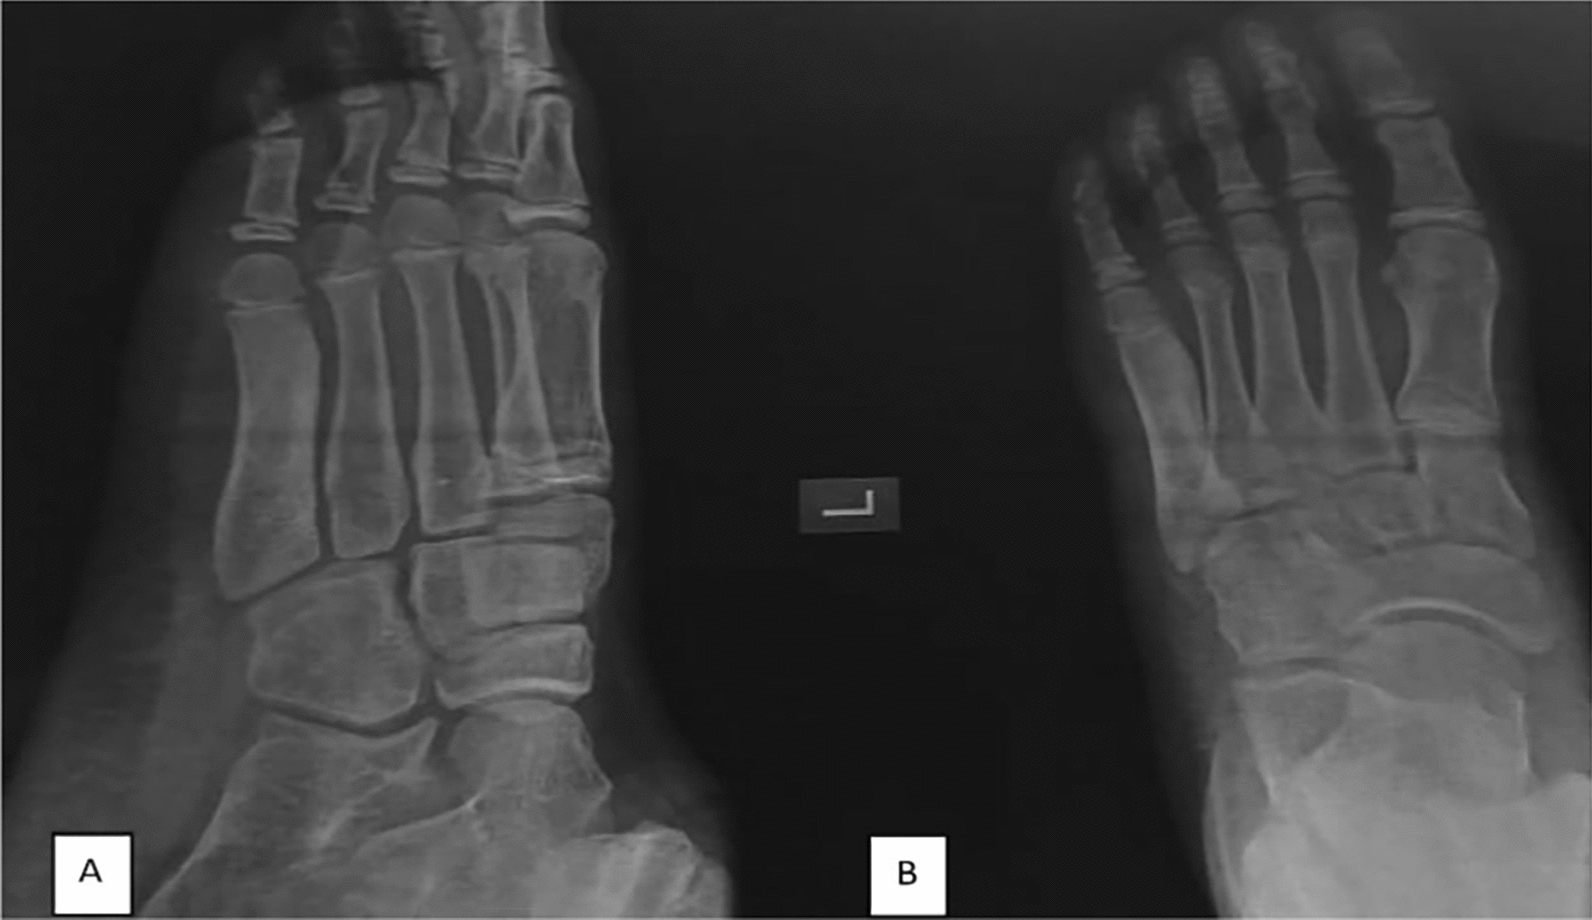

Case presentation: We report the case of a 14-year-old Persian male athlete who presented with persistent lateral forefoot pain lasting 2 years, initially attributed to a traumatic injury. The pain was progressively worsening, nocturnal, and unresponsive to nonsteroidal anti-inflammatory drugs, deviating from the classical dramatic relief associated with this tumor. Radiographs initially showed diffuse sclerosis without a visible nidus, further complicating the diagnosis. Computed tomography imaging later identified a well-defined nidus in the neck of the fifth metatarsal, confirming osteoid osteoma. Owing to the atypical symptoms, larger lesion size (> 1.5 cm), and poor response to conservative management, the patient underwent curettage and bone grafting, leading to complete symptom resolution. Histopathology confirmed the diagnosis, and postoperative follow-up showed full recovery with no recurrence at 6 months.